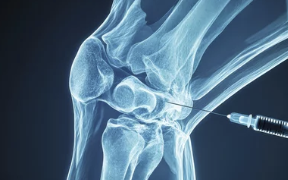

| 연골주사(히알루론산) | 관절 내 윤활 작용 → 마찰 감소, 통증 완화 |

| 고분자 히알루론산 주사 | 점도가 높아 지속시간 연장, 관절 내 환경 개선 |

| PRP (자가혈 재생 주사) | 연골 재생 유도 및 염증 억제 효과 있음 |

| 인공관절 치환술(무릎 인공관절) | 연골과 관절면 제거 후 금속+세라믹 관절로 교체 |

| 절골술 | 관절의 하중 분산을 위해 뼈를 일부 잘라 정렬 조정 |